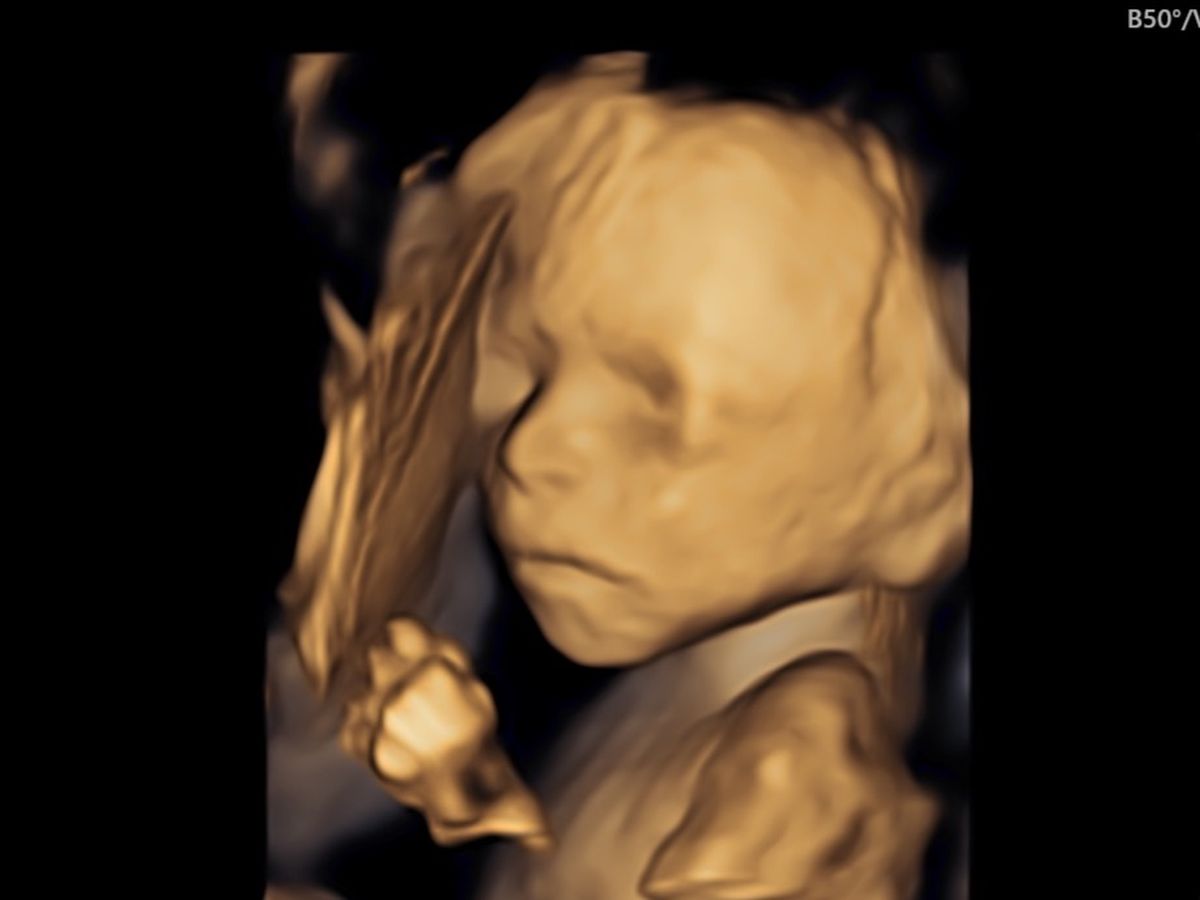

Hello everyone, my name is Haley. I am making this GoFundMe on behalf of my sister Sunny Forvilly and her husband Nick Forvilly. They recently found out that Baby Beau has a birth defect called Gastroschisis. Gastroschisis is a birth defect that causes the intestines to protrude from a hole in the abdomen, typically to the right of the umbilical cord. Occasionally, other organs are involved as well. This must be repaired surgically after birth, although surgery is not always possible immediately and depends on many factors including the amount of bowel outside of the body. While approximately 90% of affected infants survive in industrialized nations with proper medical care, there is still a 10% mortality rate due to complications or related defects and infections – even with the best medical care.